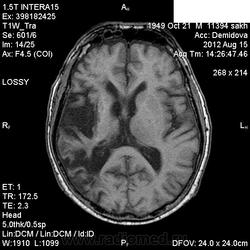

1 случай -локальная гемиатрофия.2 случай-диффузная.

Молодой человек после автомобильной аварии.3 года лежит.Двигаются только глаза.Зрелище душещипательное.

Евгений, конечно же, мои случаи не являются "чистой" атрофией-согласна.Мне пока не встречались случаи болезни Пика, Альцгеймера и другие "чистой воды" атрофии.Второй случай- состояние после длительной комы вследствие автодорожной травмы 3 года назад.Пациент проходил исследование в прошлом году , в этом родители привезли на динамику.